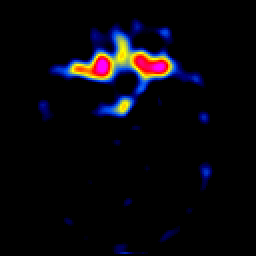

glioma overlay -- Slice #10

[Home][Help][Clinical] Slice 10